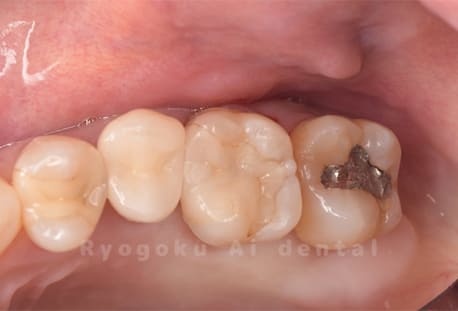

Case09

-

- 原因

- 虫歯

- 治療内容

- セラミックインレー

- 治療費用

- 77,000円

虫歯の治療を行い、白い材料での治療を希望された為、セラミックインレーで治療を行った患者さんです。

<リスク・副作用>

過度の咬合や衝撃で割れることがあります。